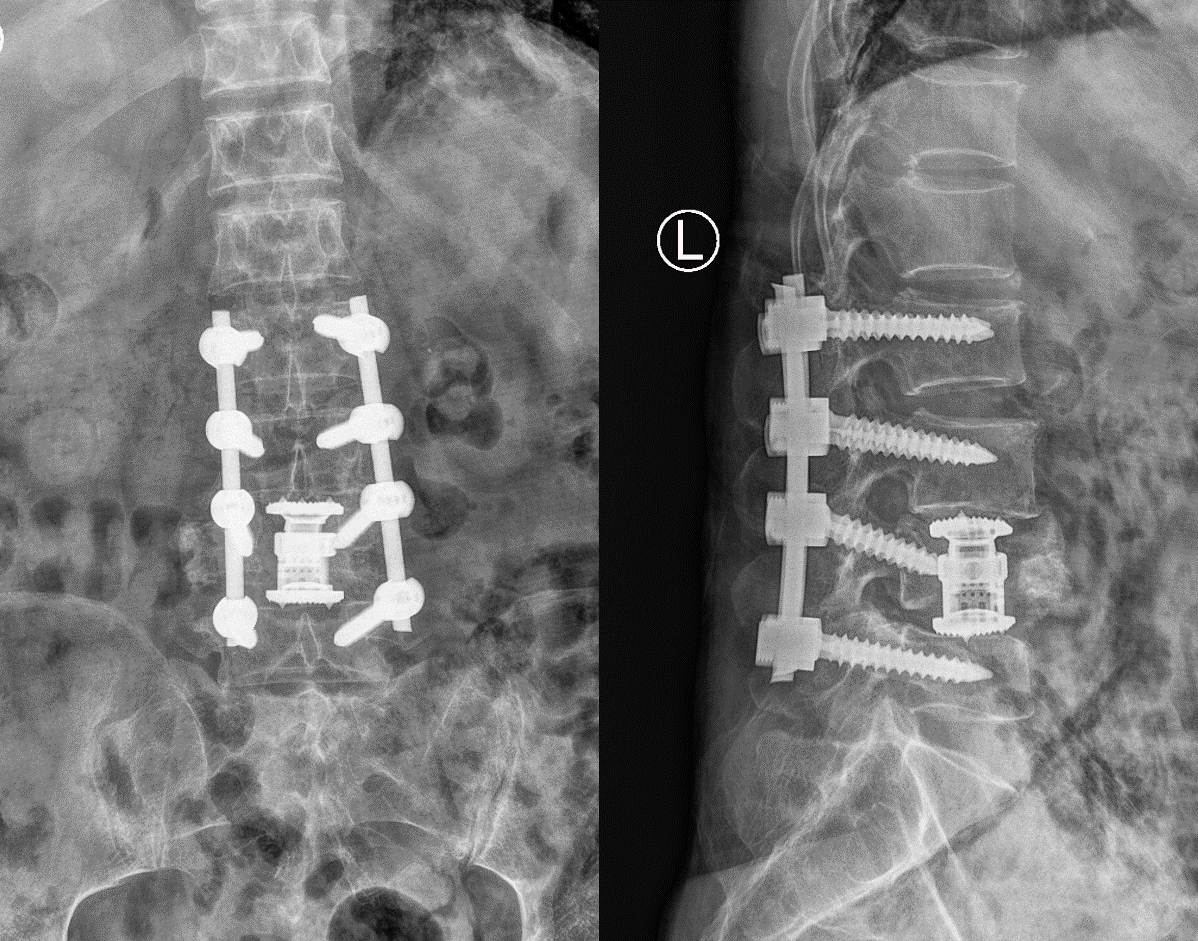

L4椎体高度恢复,脱位情况得到极大改善

患者腰椎序列恢复满意,稳定性得以重建